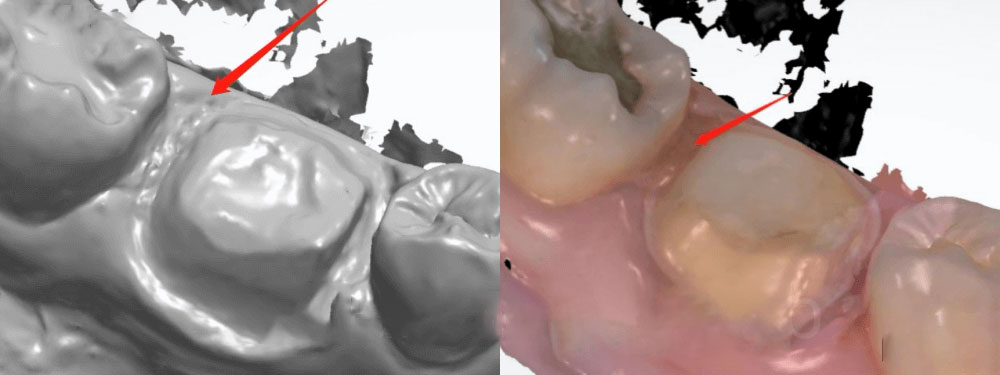

2. Checking the first-time digital scan

We can see that the first-time scan was with poor margin. The margins were covered a lot by the gum tissue. We could not clearly determine where the margin was. Therefore, we made this crown based on our experience. Please note that we normally try not to ask for new scans, because doctors are pretty busy. It is also troublesome for dentists to call back patients for new scans.

unclear margin for dental crown